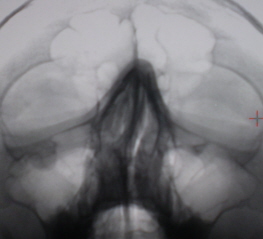

На иллюстрации 9. С обеих сторон пристеночно в гайморовых полостях определяется снижение прозрачности значительной ширины, что скиалогически создает эффект уменьшения объёма пазух.